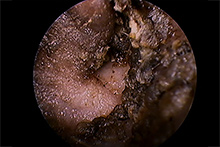

耳内視鏡(ビデオオトスコープ)で見た耳の状況

軽度~重度の症状の耳

犬の耳 1

犬の耳 1 犬の耳 2